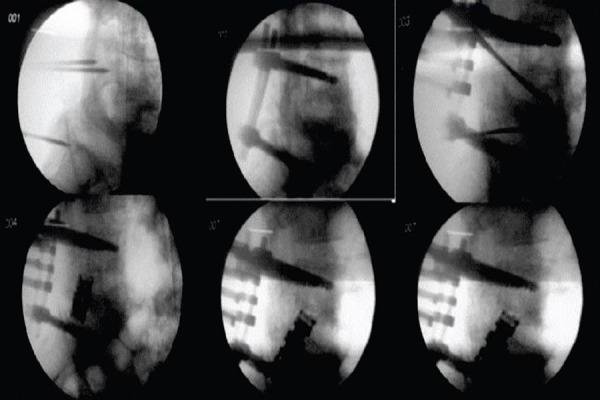

A case of young male patients aged 25 years old presented with history of injured from falling heavy object on his back. There was burst Fracture of L5 Vertebrae with grade 3 spondylolisthesis. It was completely different from the types of L5 fracture that had been published up to now. Our patient had combination of a complete burst fracture of the fifth lumbar vertebra with dislocation and complete disruption of the posterior ligamantous and bony complex between L5 and sacrum. We would like to report this unique case of comminuted burst fracture of L5 with grade III spondylolisthesis treated with reconstruction of L5 body from transforaminol approach with the good results & significant neurological improvement till his six month follow up after the operation.

A case of young male patients aged 25 years old presented with history injured from falling heavy object on his back. The physical examination revealed contusion on his back Neurological examination confirmed complete paralysis of L5 and S1 root on both sides. Loss Bladder-bowel function, sphincter tone and peri-anal sensation. Plain radiograph of lumbar-sacral spine showed the anterior dislocation of L5-S1 spondylo-listhesis approximately 75%, with the complete comminuted burst fracture of L5 vertebra.

Anterior support and reconstruction of vertebral body is of immense importance in Lumbar burst fracture, When combined with posterior short segment fixation. This can be achieved with Usage of expandable cages when opted for posterior only approach. They obviate need of anterior approach for reconstruction of vertebral body.

一名25岁的年轻男性患者,有重物砸伤背部的病史。L5椎体爆裂骨折并伴有3级椎体滑脱。这与迄今为止已发表的L5骨折类型完全不同。我们的患者为第五腰椎完全爆裂骨折合并脱位,以及L5与骶骨之间的后韧带和骨复合体完全断裂。我们想报告这例独特的L5粉碎性爆裂骨折伴III级椎体滑脱病例,采用经椎间孔入路重建L5椎体进行治疗,术后六个月随访效果良好,神经功能有显著改善。

一名25岁的年轻男性患者,有重物砸伤背部的病史。体格检查发现其背部有挫伤。神经学检查证实双侧L5和S1神经根完全麻痹。大小便功能丧失、括约肌张力及肛周感觉丧失。腰骶椎X线平片显示L5-S1椎体滑脱约75%,L5椎体完全粉碎性爆裂骨折。

腰椎爆裂骨折时,椎体的前路支撑和重建与后路短节段固定相结合非常重要。若仅选择后路手术,可使用可扩张椎间融合器来实现,这样就无需前路椎体重建手术。